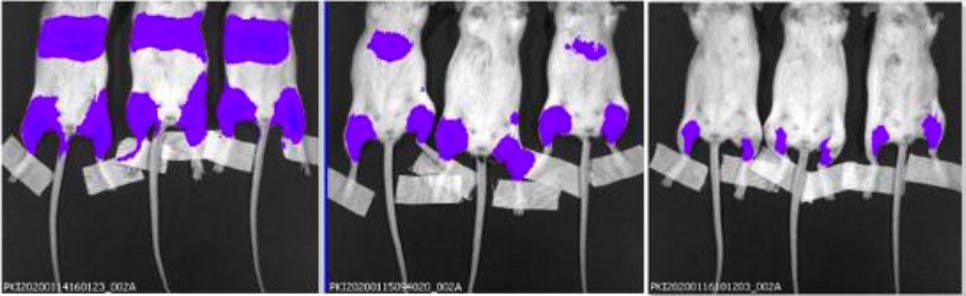

Figure 2: Bioluminescence measurement in the liver using the LNP-formulated modRNA encoding for luciferase

BALB/c mice were injected i.m. in the right and left hind leg with each 1 μg of LNP-formulated modRNA encoding luciferase. A) At 6 h, 24 h, and 48 h after injection, the luciferase expression in vivo was measured by luciferin application

19. A surrogate modRNA vaccine was tested in mice. It incorporated a modRNA encoding a gene for a protein known as luciferase. Following injection, mice could be treated such that anywhere the modRNA went, the luciferase would emit a light signal that could be detected (with low sensitivity) using specialized external whole-body imaging of the live rodents under anesthesia.

Specifically, the image in the FDA’s document is a portion of the upper image in the second column of the Japanese document (six-hour timepoint).

A close-up comparison of these two images revealed multiple concerns. The following annotated comparison of the images was produced by Dr. Bridle

23. Note that in the images shown above, the mice are lying on their bellies, so it is their backs that are showing.

24. A typical luminescence scale was added to the left side of the image, and an illustration of the anatomy of a mouse was added to the right side.

25. The image from the FDA’s version of the document is on the left and beside it is the image from the Japanese document from which the former appears to have been derived.

26. In this experiment, the site of injection of the modRNA vaccine was the large muscles of the upper hind limbs of the mice (not the shoulder muscle, as is commonly used in people).

27. Dotted red lines were added to the images to indicate where the cropping appears to have occurred.

28. An analysis of the two images seems to indicate that they represent identical mice, based on characteristics like the shape of the luminescent signals, the positions of the tails of the mice, the positions of their feet and the tape applied to the lower hind limbs, etc.

29. Several manipulations are evident. First, the image from the FDA was isolated from any relevant context. Specifically, in the Japanese document the image appeared alongside images from control mice, and from various timepoints.

30. Second, the image was rotated 90o relative to how it appeared in the Japanese document.

31. Third, the intensity of the luminescence signal was dialed down. This can be done with any bioluminescent image using the software used for acquisition of the image. When such a manipulation is done, one would expect a different file name to be applied, which is evident by the different labeling in the bottom left corners of the images.

32. Finally, and of substantial concern, the image has been cropped, apparently to exclude visualization of an obvious luminescent signal in the region of the kidneys and adrenal glands.

33. In summary, the image in the FDA’s version of the common technical document appears to be a version of the image from the Japanese document that was manipulated in numerous ways, potentially to discourage discovery that they are one and the same. It was then cropped to hide clear evidence of systemic biodistribution of the modRNA vaccine.

34. It is important to note that the images in the Japanese common technical document were also cropped to exclude approximately one-quarter of the upper bodies of the mice, including their heads. This is atypical since the convention for publishing this kind of scientific data, where systemic distribution is being evaluated, is to show the entire body of the animal. It is particularly important to know whether a novel medical intervention distributes into the brain, especially for something that is not intended to go to that location.